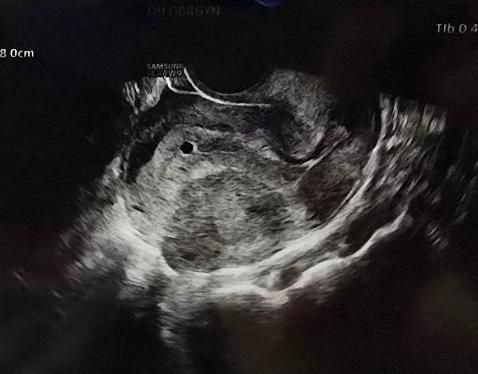

5주째 6주째 비교해서 아기집 크기가 차이없어서 계유유산 판정을 받았어요. 그런데 5주 사진보다 6주 사진이 내막도 얇아진거 같고 아기집도 자궁 아래쪽으로 내려온거 같은데 자연배출을 기다려도 될까요? 수술을 해야할까요?

6주6일차와 5주6일차(파란줄있는 사진)입니다

• 1번 째 사진